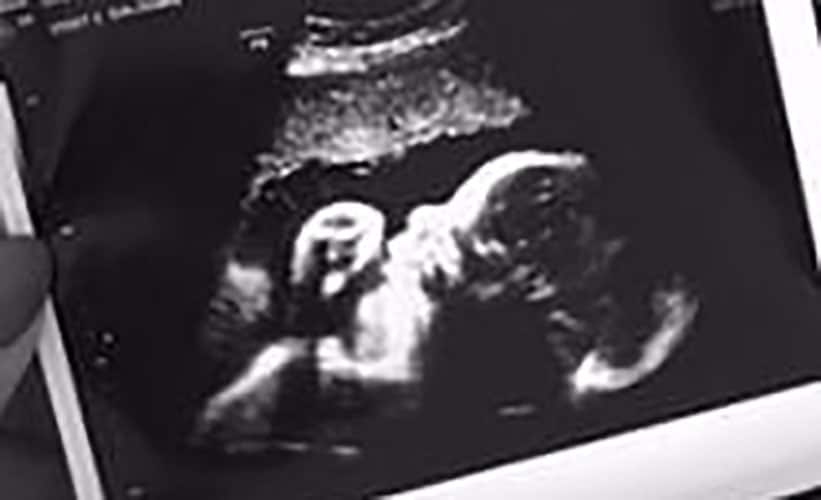

Ultraschallbilder aus dem 2. Trimester (13. bis 28. SSW)

Im 2. Trimester bekommt man oft die schönsten "Ganz-Körper" Ultraschallbilder. Das Baby ist nun so groß, dass man alles gut erkennen kann und noch nicht zu groß, so dass es noch ganz auf das Bild passt. In dieser Zeit lässt sich meist das Geschlecht bestimmen, wobei manche Babys es einfach nicht preis geben wollen und sich immer so drehen, dass man nichts erkennen kann.